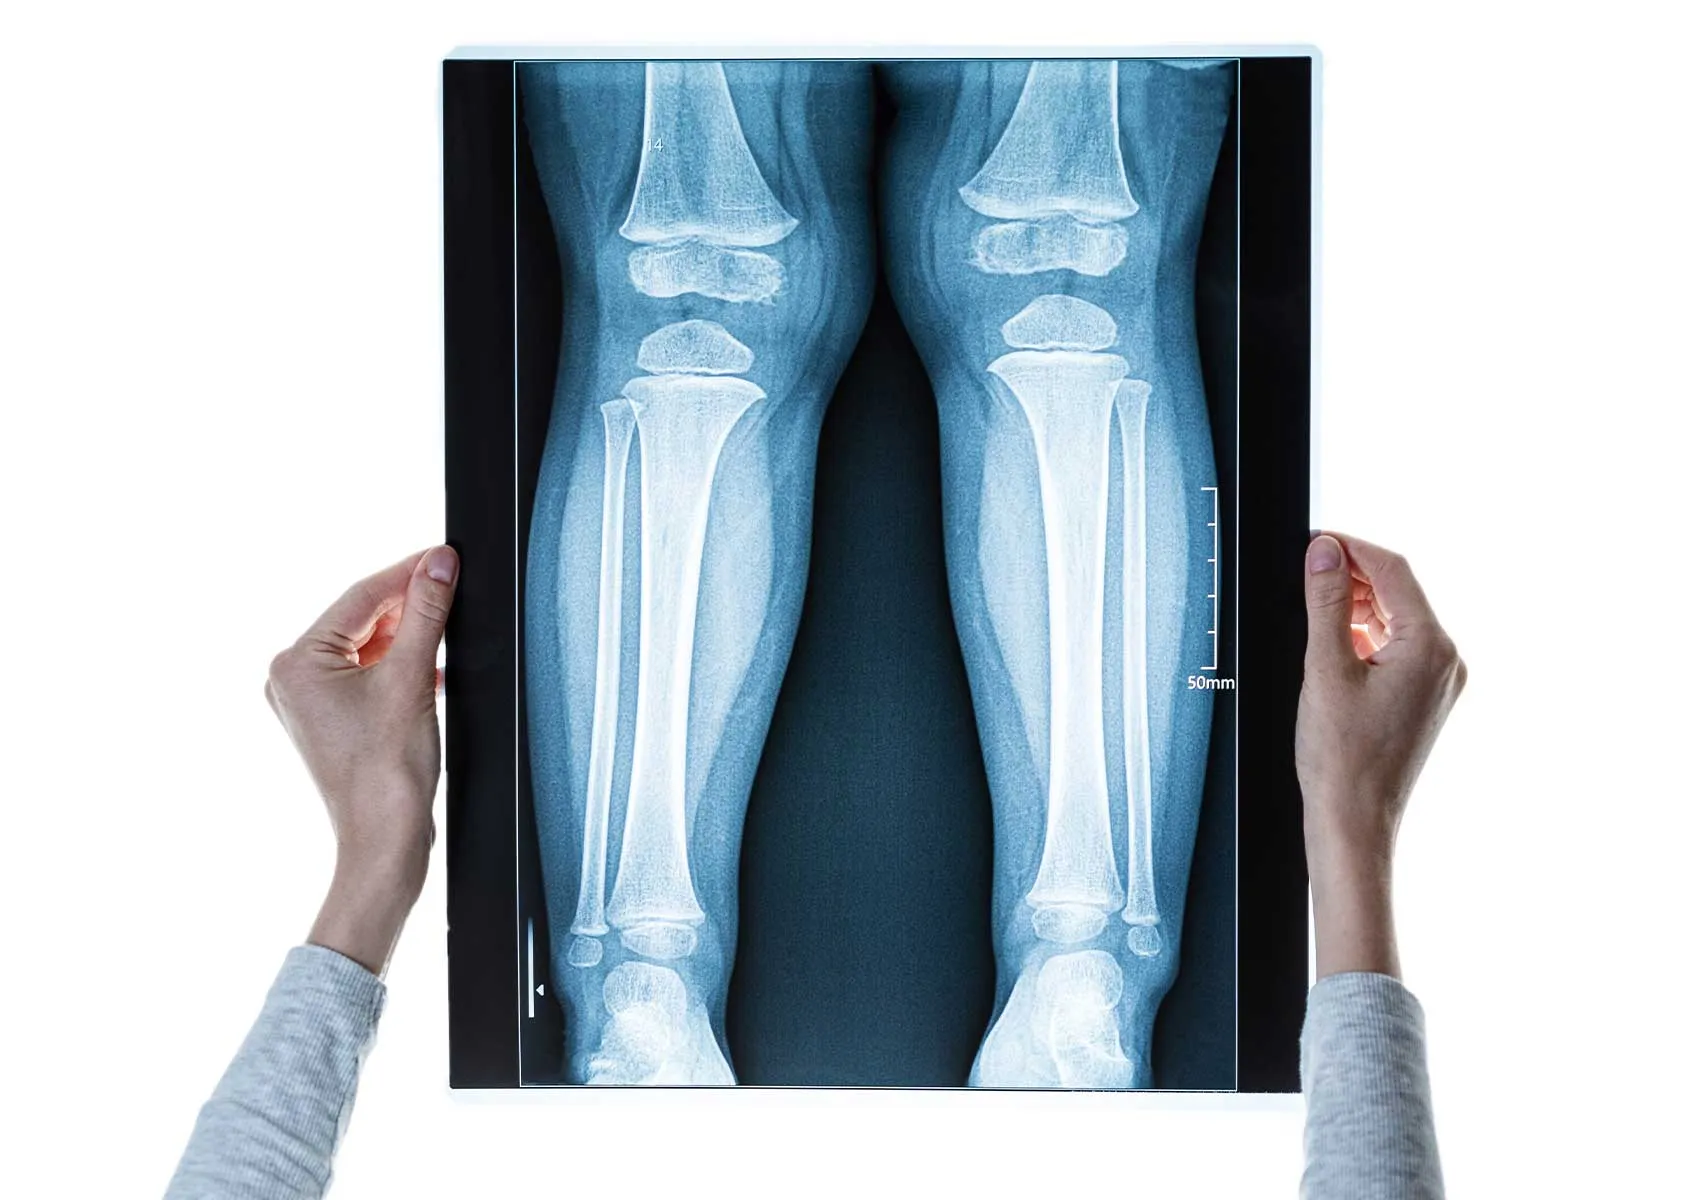

Osteotomiyi takiben kullanılan görüntüleme yöntemleri genellikle basit radyografi (X-ray), bilgisayarlı tomografi (BT) ve manyetik rezonans görüntüleme (MRG) olmak üzere üç ana gruba ayrılır.

Radyografi, osteotomi sonrası ilk ve rutin görüntüleme yöntemidir. Erken postoperatif dönemde implantların pozisyonunun değerlendirilmesi, osteotomi hattının takibi ve kemiğin kaynama seviyesinin izlenmesi için kullanılır. Özellikle anteroposterior (AP) ve lateral görüntüler temel referans sağlar. Röntgenler sıklıkla operasyon sonrası 6. hafta, 3. ay, 6. ay ve 1 yıl gibi zamanlarda çekilir.

Cerrahi sonrası ilk dönemde implant pozisyonu ve osteotomi hattının stabilitesi ile ilgili değerlendirme yapılır. İlk 6 haftalık dönemde kemiğin kaynamasında genellikle erken kalsifikasyon belirtileri röntgende görülmeye başlar. Kemik iyileşmesinin tam olması 3-6 ay arasında gerçekleşir. Bu süreçte implant çevresinde gevşeme veya olası deformite yeniden oluşumu açısından dikkatli takip yapılmalıdır.

Takip ziyaretlerinde radyolojik olarak osteotomi hattındaki kemik yoğunluğu ve kaynama derecesi karşılaştırılır. Kaynama gecikmesi veya nonunion (yetersiz kaynama) gelişme riski olan hastalarda ek takip görüntülemeleri gerekebilir. Bu gibi durumlarda tanı için BT istenebilir.